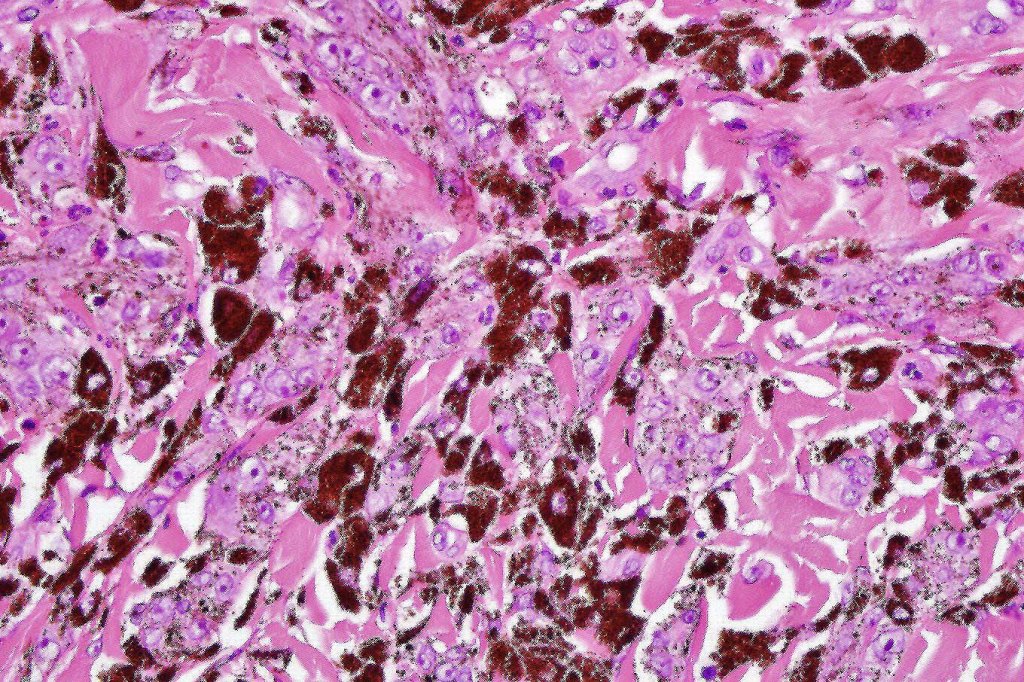

•Composed of an admixture of large epithelioid melanocytes with vesicular nuclei containing a very prominent nucleolus (fried egg cells), spindle cells, dendritic cells & melanophages

•The epithelioid cells are typically very uniform

•Few mitoses

•Perineural infiltration sometimes evident

•Absent necrosis & lymphovascular invasion